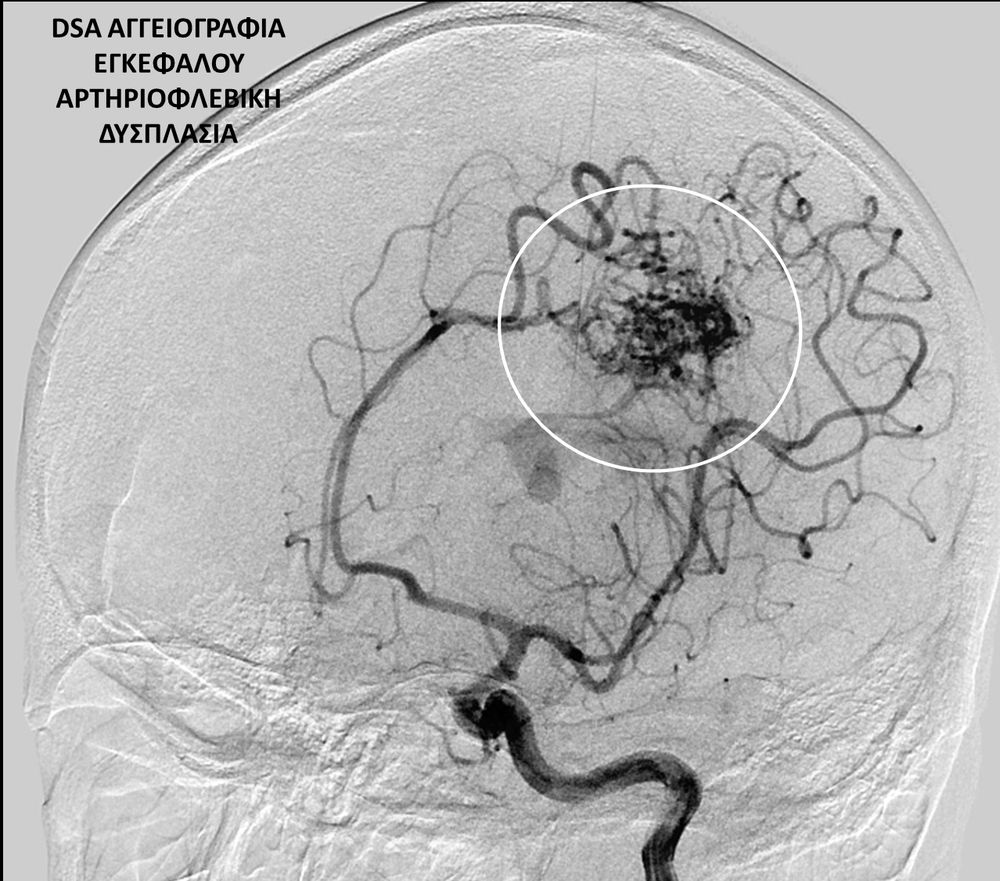

• Η ψηφιακή αγγειογραφία (DSA) αποτελεί την καλύτερη μέθοδο διάγνωσης των αγγειακών παθήσεων.Η αγγειογραφία γίνεται ως εξής: αρχικά παρακεντάται μια αρτηρία πρόσβασης, όπως η μηριαία αρτηρία στη βουβωνική περιοχή ή η βραχιόνια αρτηρία στο βραχίονα. Στη συνέχια προωθείται ένας καθετήρας προς την περιοχή του ενδιαφέροντος και γίνεται η έγχυση σκιαγραφικής ουσίας (σκιαγραφικού) με συνεχή λήψη «εικόνων» των αγγείων-στόχων.